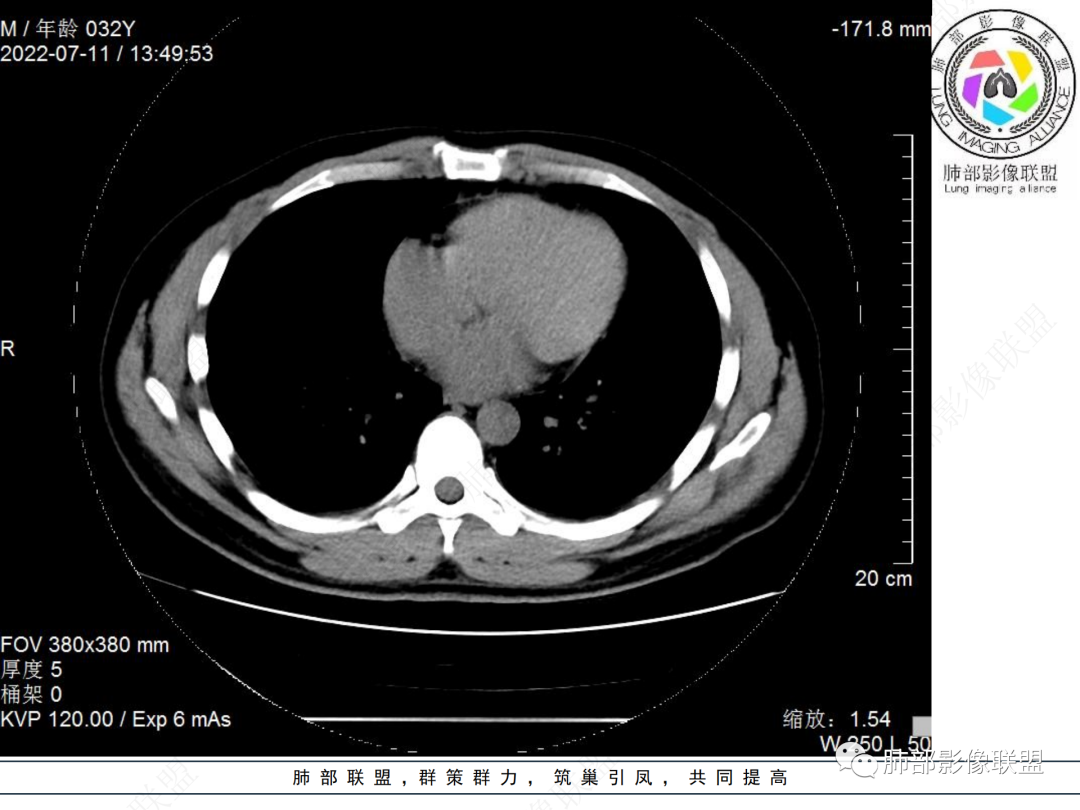

肺炎性肌纤维母细胞瘤是一种多发生于肺的间叶性肿瘤,以往临床将称为炎性假瘤、浆细胞肉芽肿、炎症性纤维肉瘤及组织细胞炎性假瘤等。2002年世界卫生组织(WHO)软组织肿瘤国际组织学分类专家组建议将其命名为炎性肌纤维母细胞瘤(Inflammatory myofibroblastic tumor,IMT),定义为“由分化的肌纤维母细胞性梭形细胞组成的,常伴大量浆细胞和/或淋巴细胞的一种肿瘤”。文献报道IMT的发病机制可能与病毒和支原体感染有关,表现为机体对炎症的一种异常或过度反应。最终激活具有增殖潜能的肌纤维母细胞过度增生或失控增长而形成。肺IMT较为常见,IMT是16岁以下儿童最常见的原发性肺肿瘤,占儿童肺良性肺肿瘤的50%。大多数报告病例都在40岁以下。

IMT常表现为边缘清晰的周围型结节或肿块,一般体积相对较大。大约10%-20%发生于支气管及气管腔内,表现为中央型病变,一般为单发。IMT胸部CT显示90%为单发结节或肿块。

IMT的影像表现缺乏特异性。部分肿块表现为桃尖征和边缘平直征,界限可清晰有分叶状轮廓,也可界限模糊具有粗长毛刺。肺IMT的CT表现特征与病理具有相关性,可伴有囊变、局灶性钙化、肺实变和空洞样表现。CT增强扫描呈多样性,强化形态和CT值增加幅度呈多样性。粘液血管型增强CT实性成分呈明显花环样强化,静脉期强化进一步增高,此与毛细血管增生与血管管壁通透性增加有关。囊性低密度无强化区镜下为黏液样变形、炎性渗出或坏死。梭形细胞密集型增强扫描呈渐进性延迟强化特点,但强化程度弱于黏液血管型。少细胞纤维型增强扫描实性成分强化不明显或呈轻中度强化。PET/CT上IMT具有很高的SUV值。IMT高摄取的可能原因可能与激烈炎症导致的代谢活动增加有关,这使得IMT与其他恶性肿瘤难以区分。

肺IMT作为一种少见的疾病,具有潜在的恶性倾向,手术切除是治疗肺IMT的有效手段,但存在局部复发的风险,所以术后长期的密切随访是必要的。